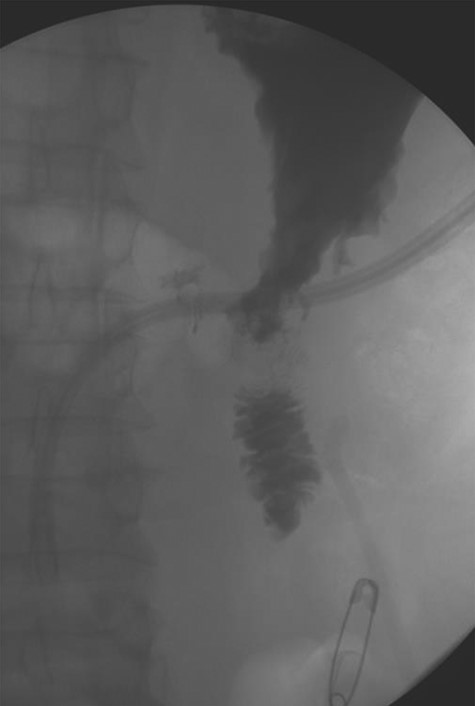

A 56-year-old African American male presented in 2015 with abdominal pain, with associated melena and hematochezia. The patient has a history of chronic back pain for which he takes 600 mg ibuprofen daily, alcohol abuse, tobacco use and a previous GI bleed in 2011, which necessitated 6 units (U) of packed red blood cells (PRBCs) and emergency therapeutic endoscopy. The patient was found to be hypotensive to 76/56 mm Hg, and hemoglobin (Hgb) was found to be 9.4 g/dl, from a previous baseline of 10.6 g/dl. His rectal examination was guaiac positive. A repeat Hgb was found to be 6.5 g/dl. The patient was given 3 U of PRBC and an emergency endoscopy was performed. On endoscopy, the patient was found to have a 6 cm gastric ulcer with an associated vessel underneath of a large clot. Due to the high risk nature of the bleed, it was felt by the gastroenterologist that the patient should undergo an endovascular angioembolization (Fig. 1). The patient was brought to the Interventional Radiology Suite for the procedure. The patient’s right common femoral artery was accessed and the celiac trunk was selected. A subselective common hepatic arteriogram was performed, which demonstrated active extravasation arising from the proximal aspect of the GDA. The GDA was then coil embolized both proximal and distal to the site of bleeding using five microcoils. Repeat arteriogram demonstrated no further opacification of the GDA and no further extravasation (Fig. 2).

Demonstrating coil embolization of the GDA with no opacification